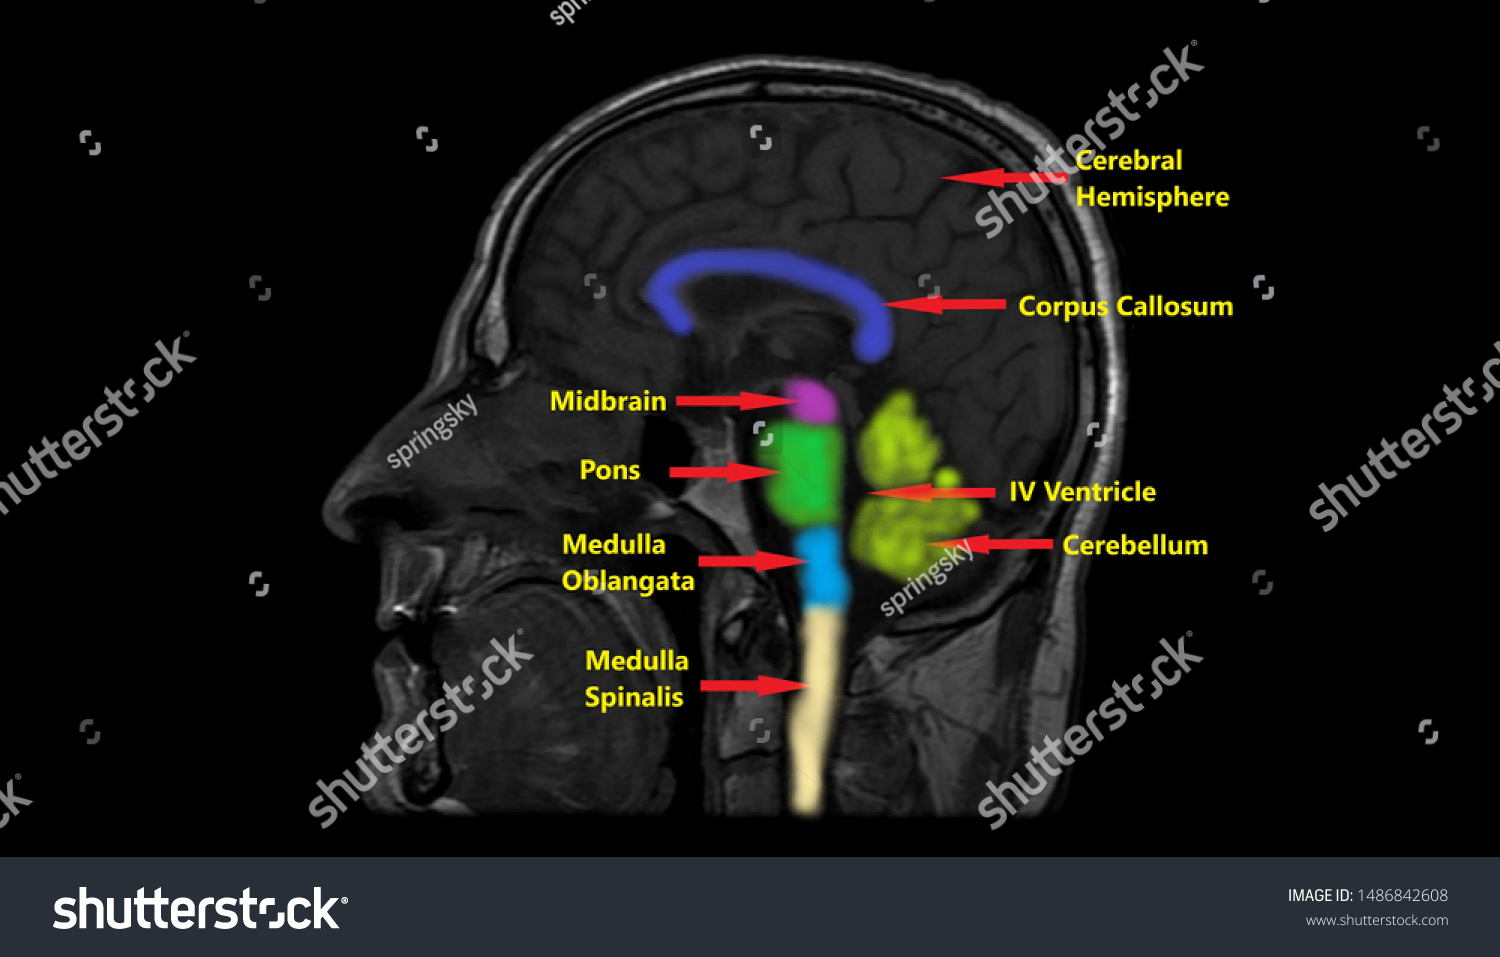

Discover the sophistication of annotated illustration of the jaw's anatomy | stable diffusion online with our curated gallery of numerous images. featuring elegant examples of photography, images, and pictures. ideal for luxury lifestyle publications. Browse our premium annotated illustration of the jaw's anatomy | stable diffusion online gallery featuring professionally curated photographs. Suitable for various applications including web design, social media, personal projects, and digital content creation All annotated illustration of the jaw's anatomy | stable diffusion online images are available in high resolution with professional-grade quality, optimized for both digital and print applications, and include comprehensive metadata for easy organization and usage. Our annotated illustration of the jaw's anatomy | stable diffusion online gallery offers diverse visual resources to bring your ideas to life. Professional licensing options accommodate both commercial and educational usage requirements. Cost-effective licensing makes professional annotated illustration of the jaw's anatomy | stable diffusion online photography accessible to all budgets. Regular updates keep the annotated illustration of the jaw's anatomy | stable diffusion online collection current with contemporary trends and styles. Multiple resolution options ensure optimal performance across different platforms and applications. Time-saving browsing features help users locate ideal annotated illustration of the jaw's anatomy | stable diffusion online images quickly. Whether for commercial projects or personal use, our annotated illustration of the jaw's anatomy | stable diffusion online collection delivers consistent excellence.

![[DIAGRAM] Blank Diagram Of Human Skull - MYDIAGRAM.ONLINE](https://fc05.deviantart.net/fs71/i/2012/270/0/0/annotated_human_skull_anatomy___side_view_by_shevans-d5g1lgl.png)